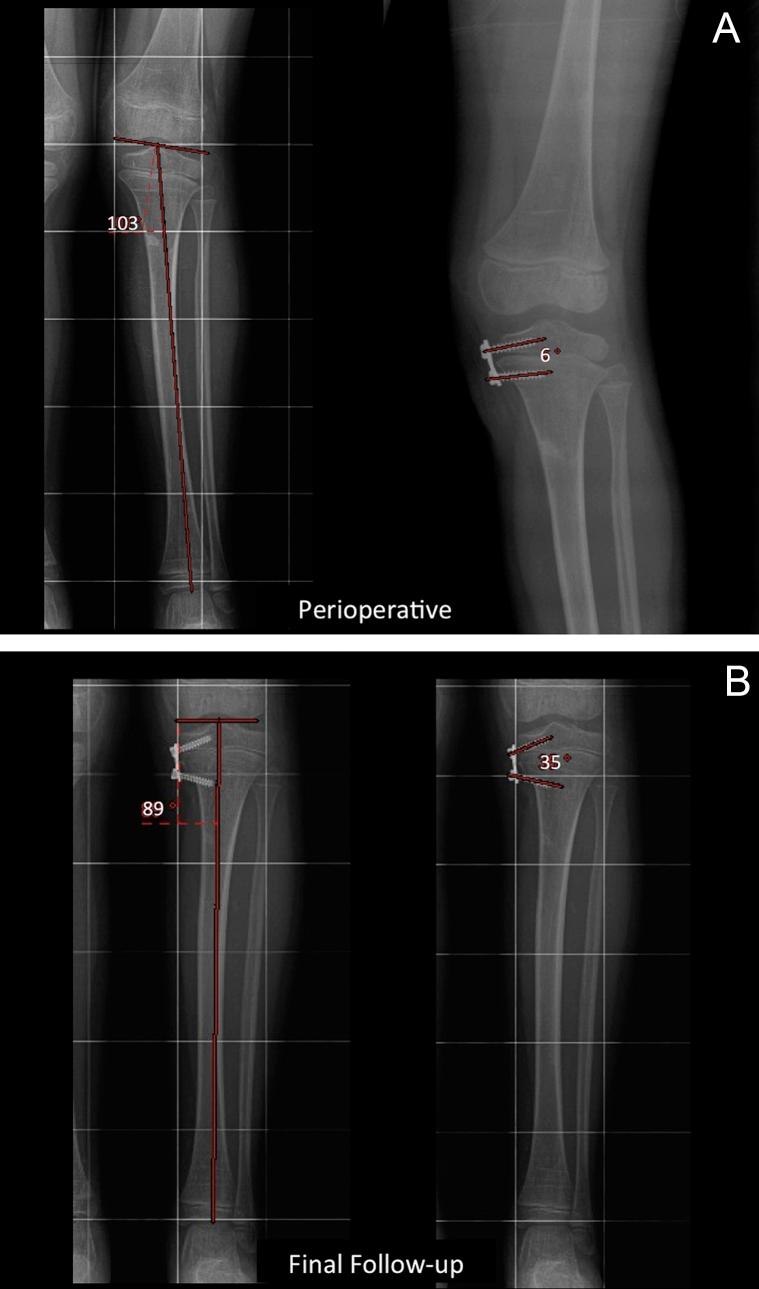

It is known that the screws of the eight-plate hemiepiphysiodesis construct diverge as growth occurs through the physis. Our objective was to investigate whether there is a correlation between the amount of change of the joint orientation angle (JOA) and that of the interscrew angle (ISA) of the eight-plate hemiepiphysiodesis construct before and after correction.

After the institutional review board approval, medical charts and X-rays of all patients operated for either genu valgum or genu varum with eight-plate hemiepiphysiodesis were analyzed retrospectively. All consecutive patients at various ages with miscellaneous diagnoses were included. JOA and ISA were measured before and after correction. After review of the X-rays, statistical analyses were performed which included Pearson correlation coefficient and regression analyses.

There were 53 segments of 30 patients included in the study. Eighteen were males, and 12 were females. Mean age at surgery was 9.1 (range 3-17). Mean follow-up time was 21.5 (range, 7-46) months. The diagnoses were diverse. A strong correlation was found between the delta JOA (d-JOA) and delta ISA (d-ISA) of the eight-plate hemiepiphysiodesis construct (r = 0.759 (0.615-0.854, 95%CI), p < 0.001). This correlation was independent of the age and gender of the patient.

There is a strong correlation between the d-ISA and the d-JOA. The d-ISA follows the d-JOA at a predictable amount through formulas which regression analysis yielded. This study confirms the clinical observation of the diverging angle between the screws is in correlation with the correction of the JOA.